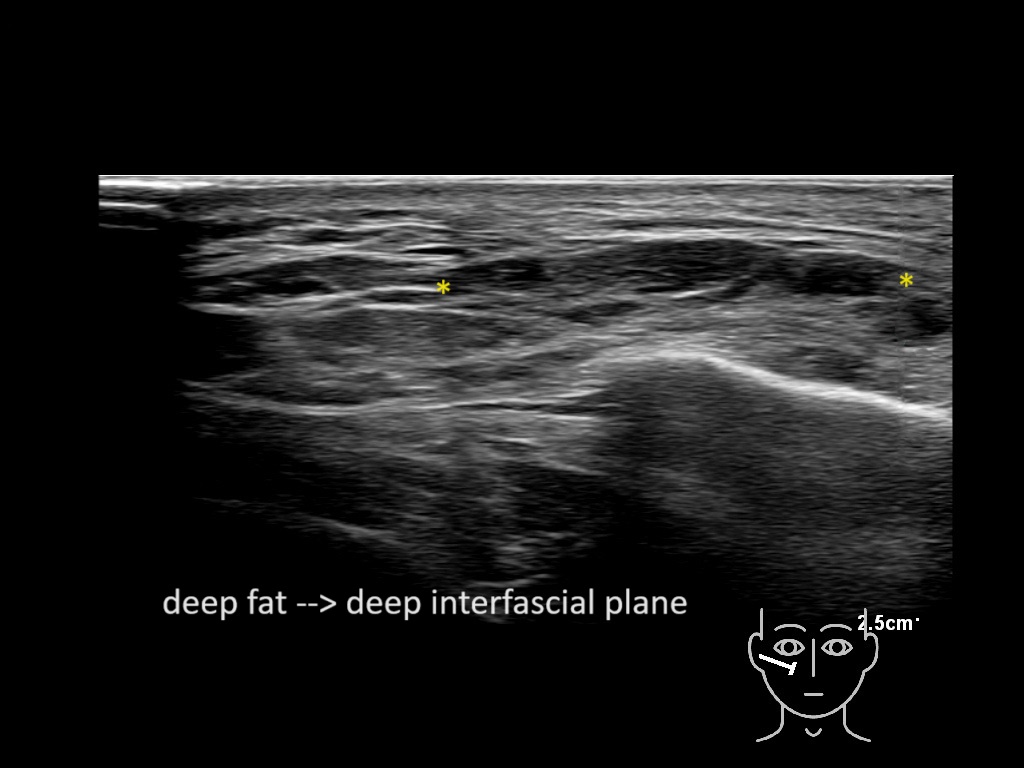

Filler behavior - Temple zygoma US

Study the first image to recognize the different layers. If you are sure about the layers, swipe to the second image to view the answer (if applicable).

Hover over an image to view the secondary image or click on the image title for more information.